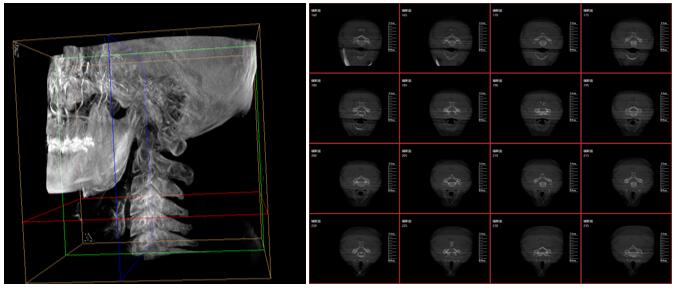

PLX7500三維成像圖片

這款新型三維C型臂—PLX7500集成手術(shù)導(dǎo)航和手術(shù)機器人接口,可無線傳輸三維重建的圖像數(shù)據(jù)至導(dǎo)航設(shè)備,無需額外手動注冊步驟,實現(xiàn)術(shù)中圖像的實時引導(dǎo)規(guī)劃,輔助醫(yī)生精準定位手術(shù)器械和植入物,為實現(xiàn)手術(shù)室的數(shù)字化和智能化拓展提供可能。

采用30cmx30cm的動態(tài)平板探測器,輸出高分辨率、大尺寸的二維、三維圖像。超高16比特灰階度,高動態(tài)范圍清晰顯示植入物的位置和輪廓。

強大的圖像后處理功能軟件,自動調(diào)整比較好的圖像窗寬窗位,顯著降低螺釘?shù)慕饘賯斡埃档蛨D像區(qū)域噪點,進一步優(yōu)化圖像品質(zhì)。